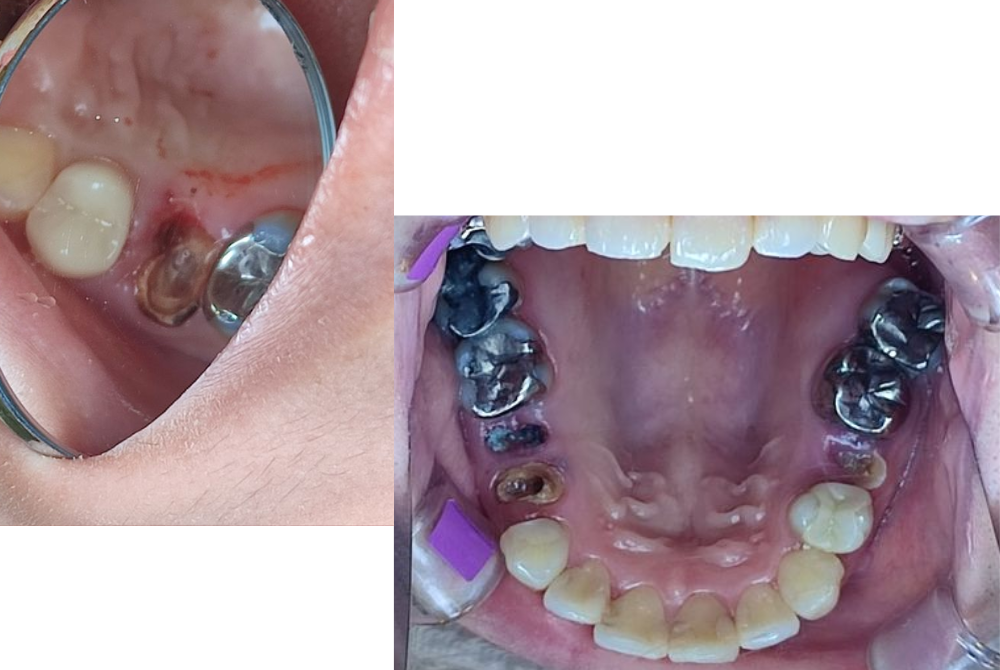

C4(歯の根まで進行した虫歯)

歯がほとんど崩れ、根しか残っていない状態です。痛みが引く場合もありますが、それは神経が死んでしまった証拠。 抜歯が避けられないこともあり、早期発見が何より大切です。